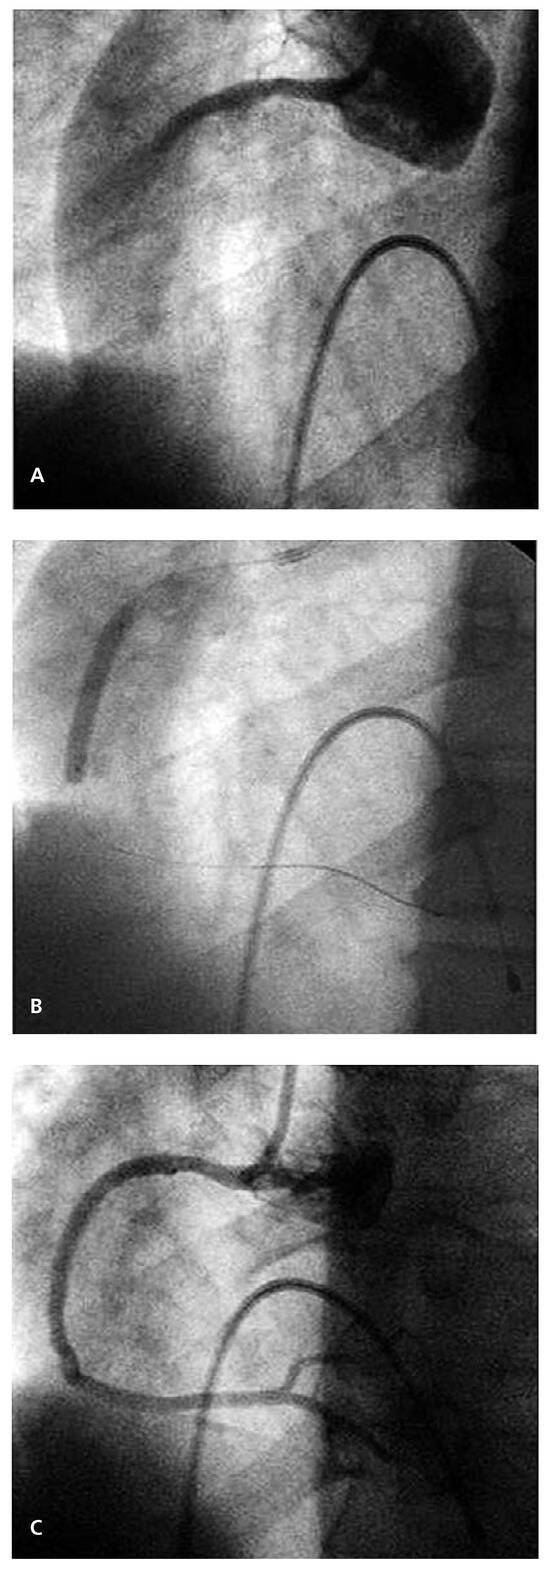

Case report A 22-year-old male experienced a presyncopal spell while studying for a university examination [...]